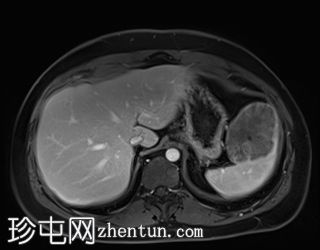

冠状位

T2加权像

T1低信号,T2低信号为主的脾脏肿块,内部可见T2高信号分隔,呈进行性强化。肿块中央可见星状瘢痕。

脾脏硬化性血管瘤样结节性转化(SANT),9.8 cm肿块

顾名思义,脾脏硬化性血管瘤样结节性转化(SANT)是一种纤维性血管病变。本病例展示了SANT的一些典型影像学特征,包括边界清晰的病灶,中央可见瘢痕,以及呈放射状进行性强化。这些特征使得术前MRI诊断较为明确。尽管SANT是一种良性病变,但大多数患者仍需行脾切除术以明确病理诊断。